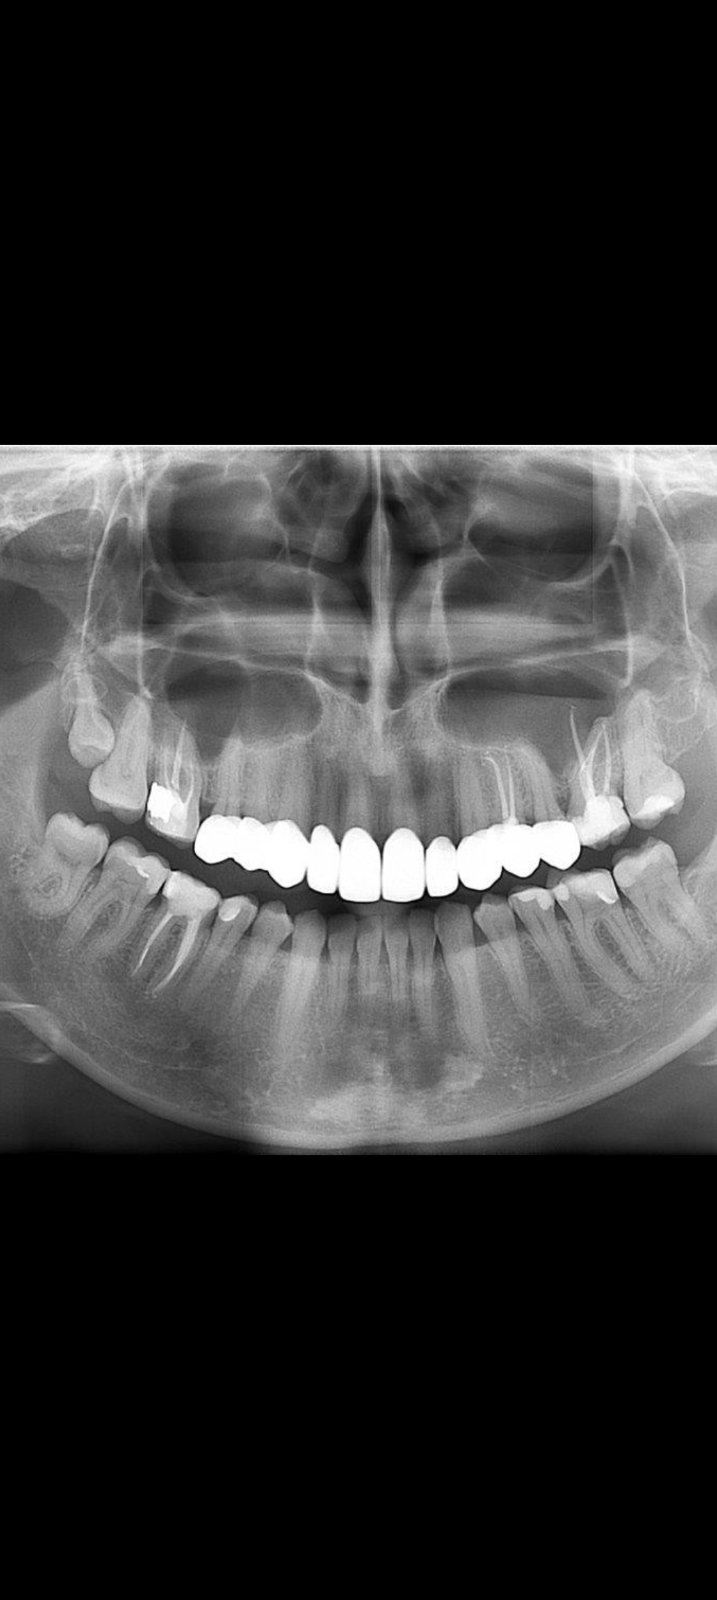

@abx lepšie, z vášho pohľadu ako keď sa pozeráte na rtg, hore vľavo začnem osmička von, vyzerá ze robí pro lem sedmicke alebo začne lebo už na tej sedmičke zozadu vyzerá ze sa začína robiť kaz lebo sa to zle čistí, šestka ten mŕtvy zub na tej strane nemá doplnené kanaliky podľa tohto ale nevyzerá zápal a keď nerobí problém je to v poriadku, trebalo by rtg len na ňu ale nevyzerá, na druhej strane hore sedmička ma asi kaz smerom k šestke, dole na tej istej strane tiež sedmička vyzerá na kaz smerom k šestke, päťka na tej strane tiež, na opačnej strane tiež päťka a aj šestka a osmička vyzerá ze ma kaz. Na to by ale lepšie bolo spraviť zahryzove snímky, lebo to môže byť len tieň a na hodnotenie kazov sú lepšie. Mostík vyzerá dobre. Zvyšné mŕtve zuby tiež sú pekne zaplnené a nevyzerá ze by bol okolo nich zápal. Ak sa doplnia tie rtg a budú v poriadku je to super. Na pár miestach vyzerá byt kameň ale dentalna hygiena to spraví. Ak ešte nebola

Nedá sa zväčšiť ak by bol v komentári šiel by ale čo vidím tak ta osmička hore moze ostat ak nerobí problém, na opačnej strane šestka ma okraj okolo korenou tmavší ale to sa ťažko pozera na tak malom na väčšom by bolo lepšie vidno, môže to byť len tien, dole na tej strane rtg je to strana pravá, na šestke tiež niečo vyzerá ale nie je to 100%, na druhej strane šestka vyzera ze ma zápal okolo koreňov, sedmička ma asi kaz a osmička ak nerobí problém nechať tak. Trebalo by zahryzove snímky a na tie mŕtve aj rtg kde je celý zub aby sa to pozrelo. Mostík vyzerá fajn podľa tohto len ako je ten mŕtvy by to chcelo lepší rtg

Ale naozaj je mala ta fotka a tým ze sa nedá zväčšiť sa to aj ťažšie posudzuje